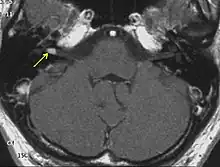

![]() | |

| Figure of various morbidities associated with neurofibromatosis type II.[1] | |